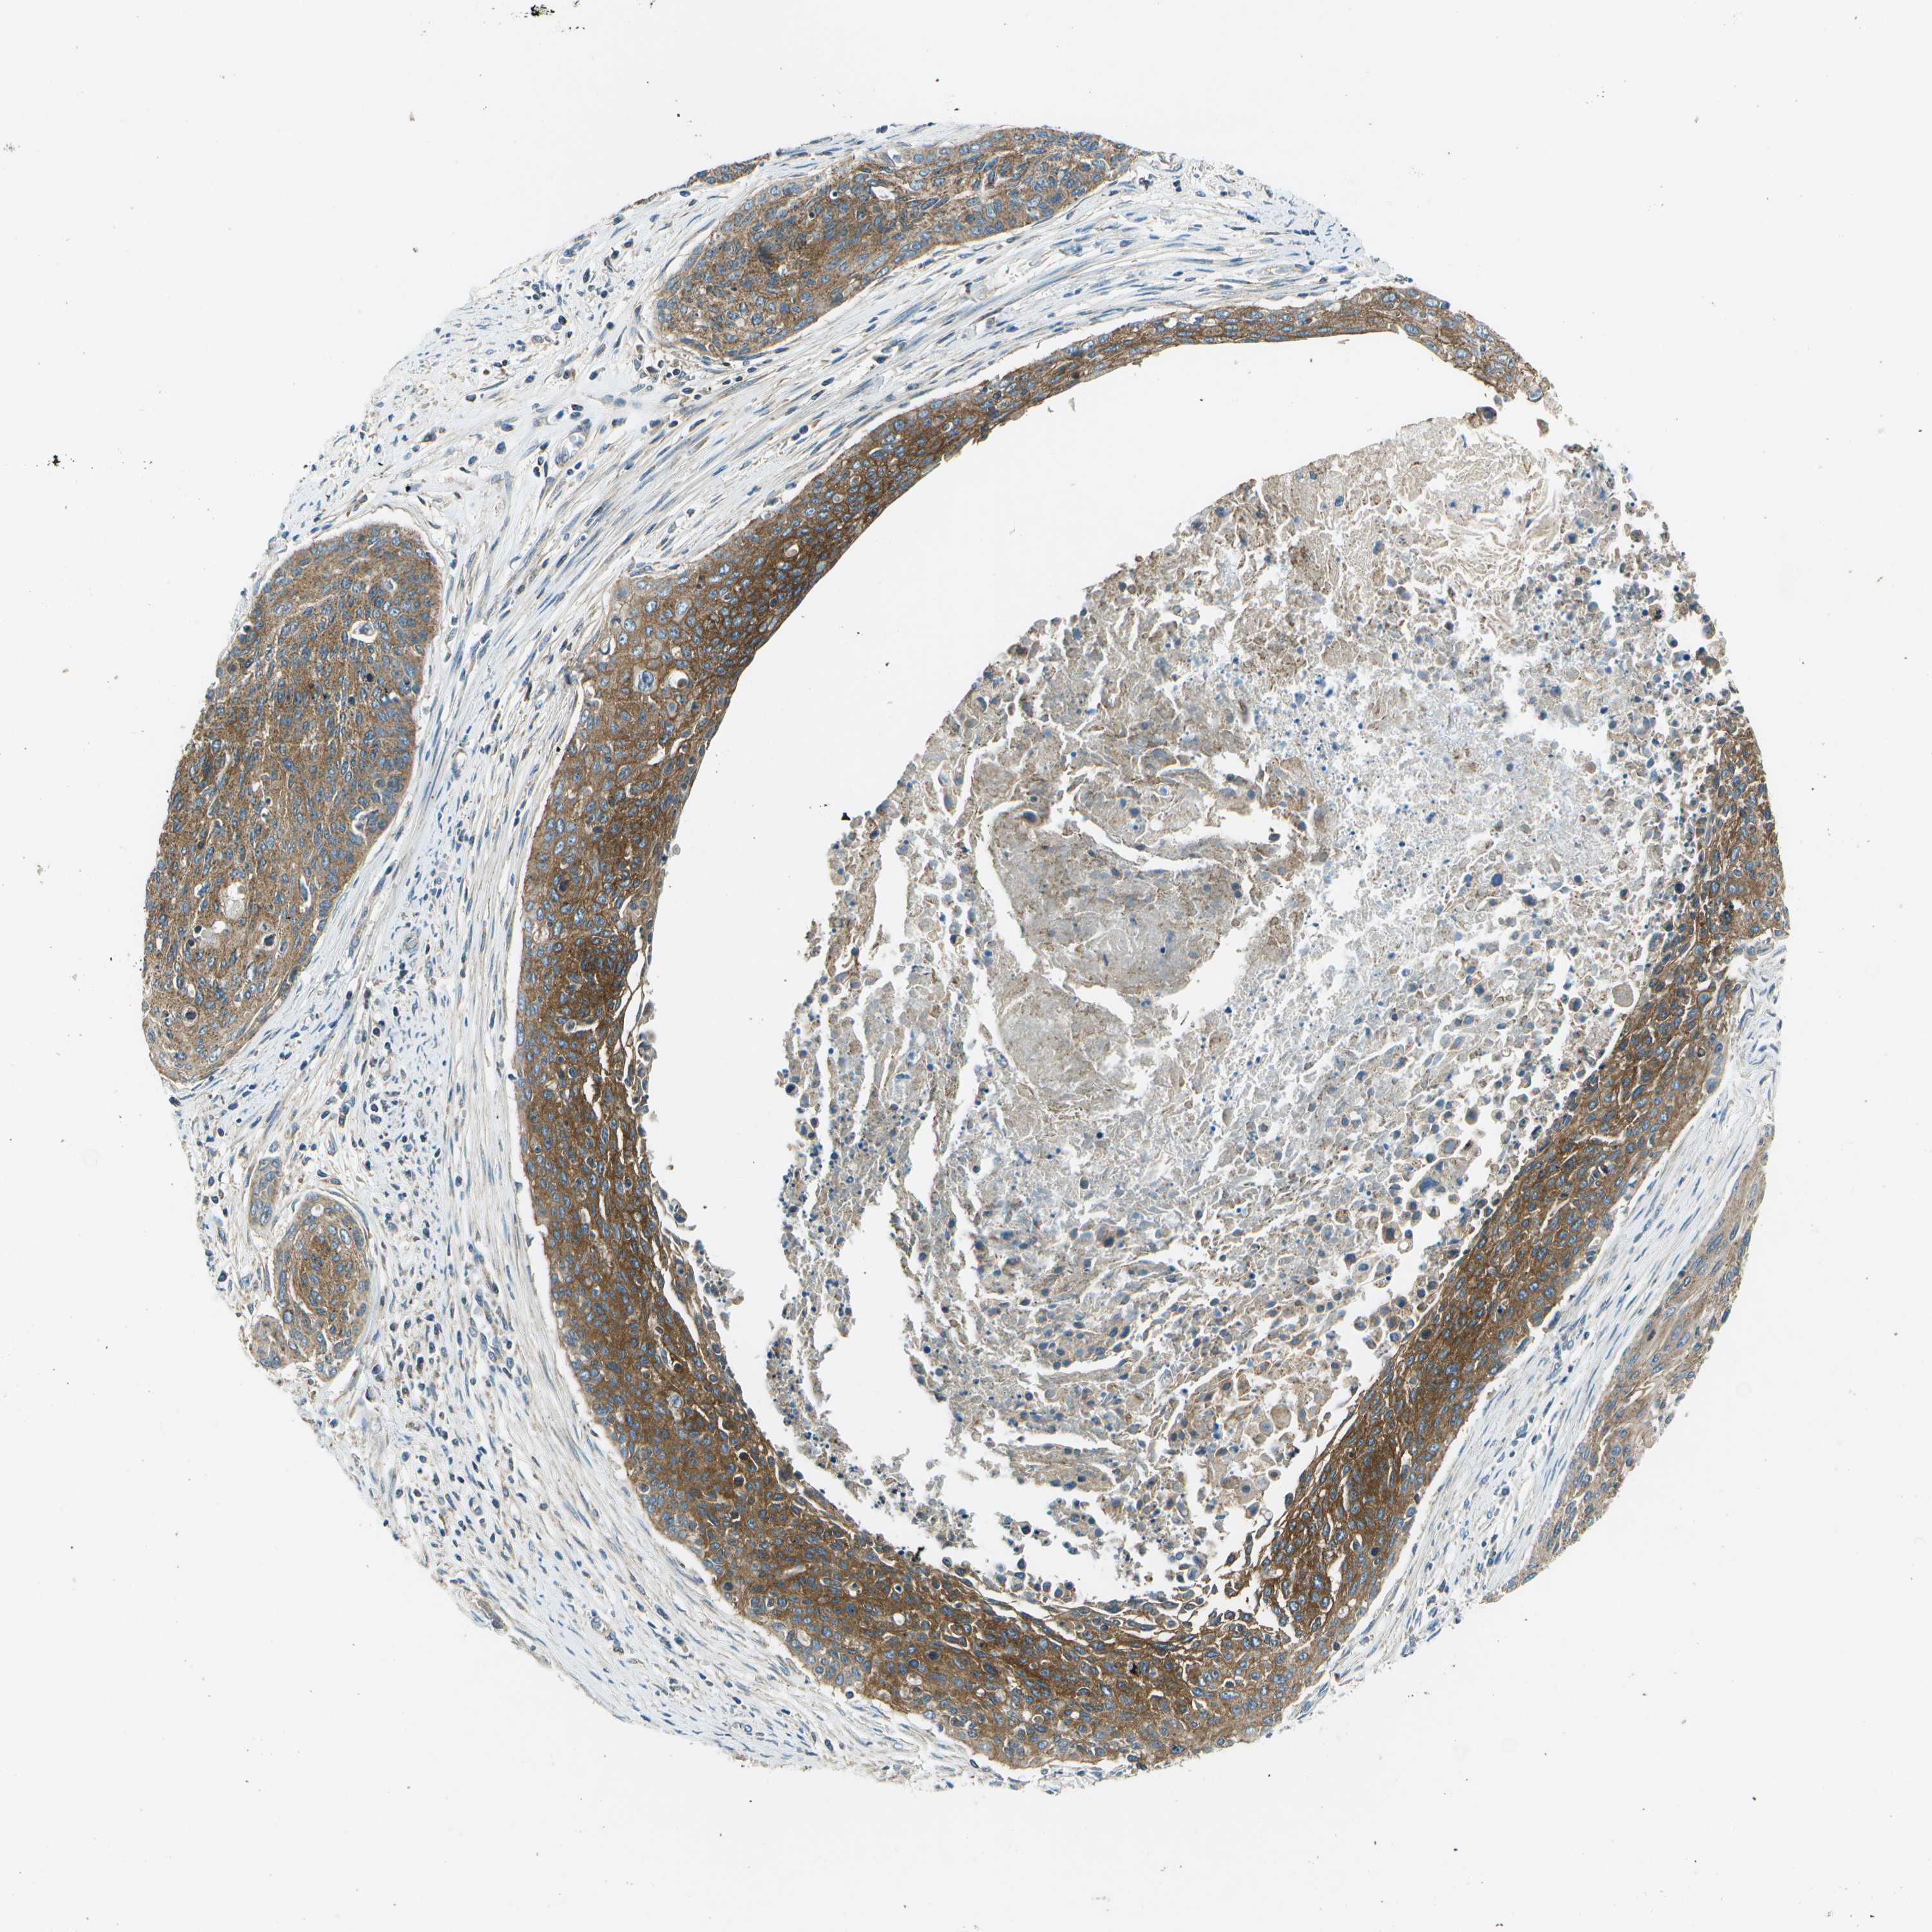

CERVICAL CANCER - Protein expressioni

A mouse-over function shows sample information and annotation data. Click on an image to view it in a full screen mode. Samples can be filtered based on level of antibody staining by selecting one or several of the following categories: high, medium, low and not detected. The assay and annotation is described here.

Note that samples used for immunohistochemistry by the Human Protein Atlas do not correspond to samples in the TCGA dataset.

Antibody stainingi

Antibody staining in the annotated cell types in the current human tissue is reported as not detected, low, medium, or high, based on conventional immunohistochemistry profiling in selected tissues. This score is based on the combination of the staining intensity and fraction of stained cells.

Each image is clickable and will lead to virtual microscopy that enables deeper exploration of all samples and also displays staining intensity scores, fraction scores and subcellular localization as well as patient and tissue information for each sample.

Antibody HPA014547

Staining

High

Medium

Low

Not detected

Intensity

Strong

Moderate

Weak

Negative

Quantity

>75%

75%-25%

<25%

None

Location

Nuclear

Cytoplasmic/membranous

Cytoplasmic/membranous,nuclear

Squamous cell carcinoma, NOS

Adenocarcinoma, NOS